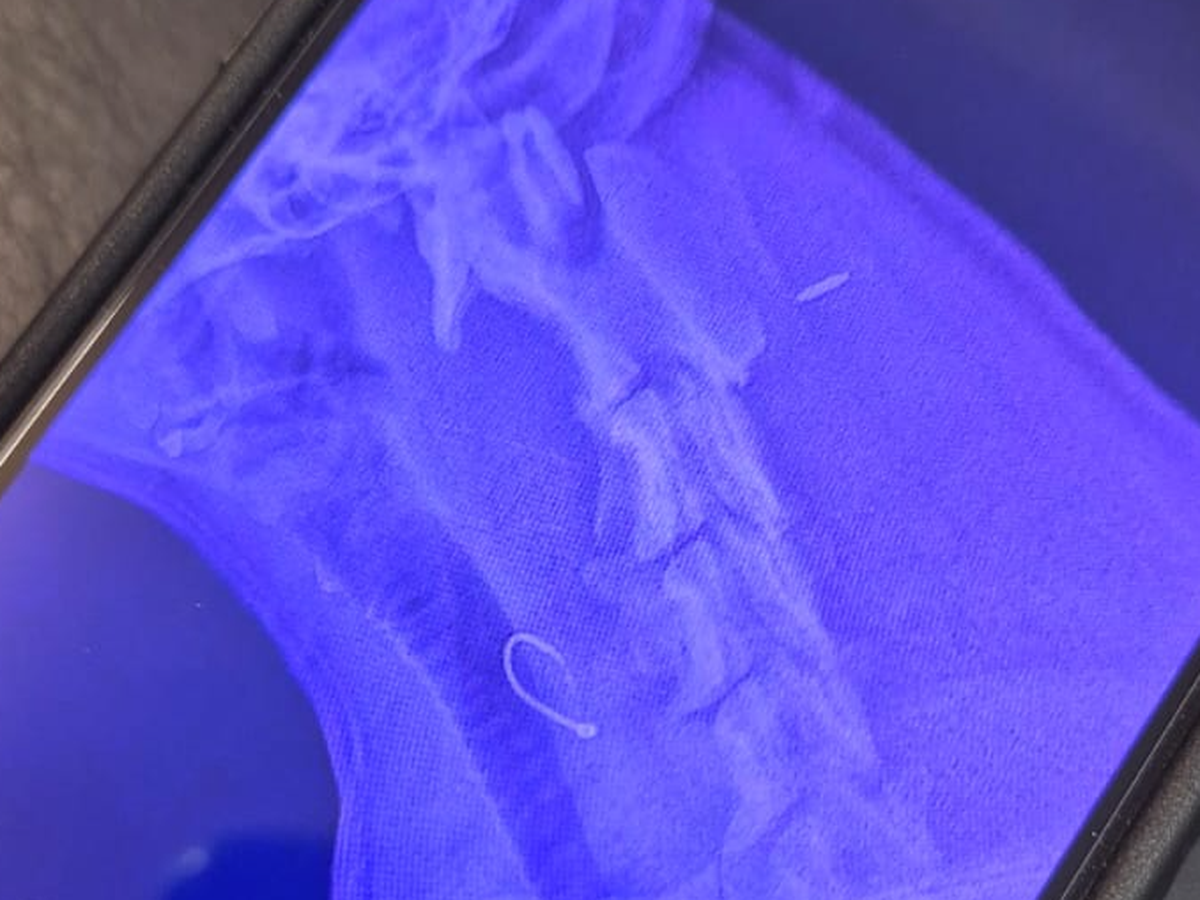

My name is Michelle I'm raising funds for Lissy Harris she swallowed a fishing hook today and is currently in surgery the vets are trying to remove the hook but are struggling to locate it.